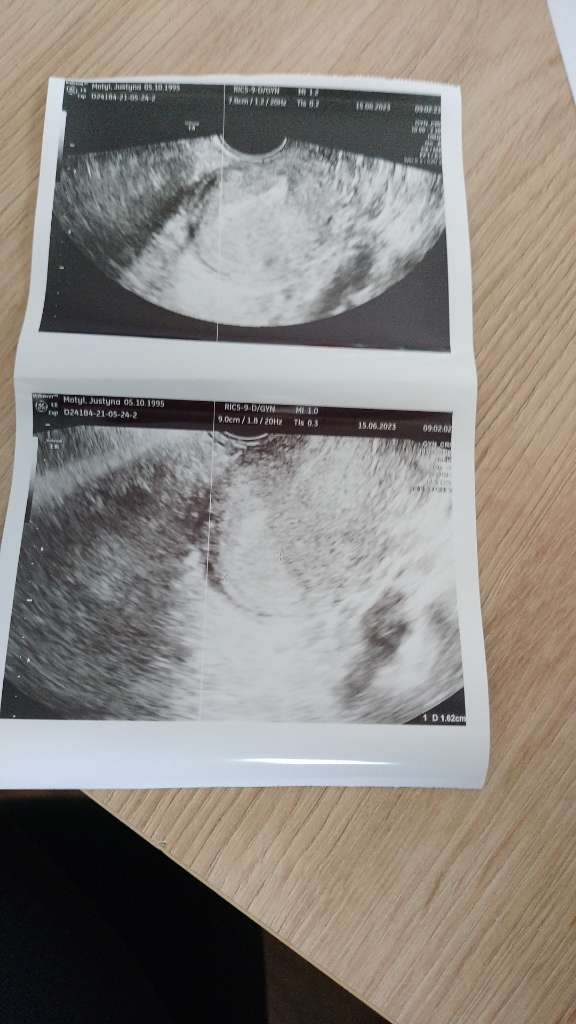

i są przypadki gdzie przy 1500 nie ma a na następny dzień jest ale podobno nie najlepsze USG ma więc czekam na poniedziałekWiem, rozumiem tylko przy becie ponad 1000 to już powinien być pęcherzyk w macicy widoczny. Ale dużo zależy też od sprzętu, także trzymam kciuki, żeby wszystko było dobrze!!!![]()